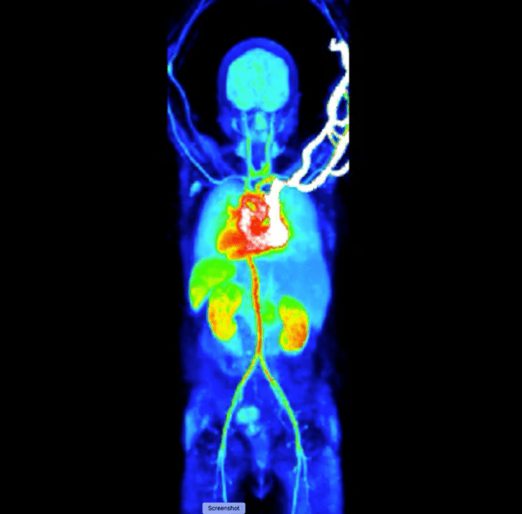

Vuonna 2022 Valtakunnallisessa PET-keskuksessa alkoi uusi aikakausi Suomen ensimmäisen koko kehon PET-kameran asentamisen myötä. Uudenlaiseen sensoritekniikkaan perustuva PET-kamera on useita kertoja vanhoja herkempi, ja kaikki tärkeimmät elimet aivoista alkaen mahtuvat kerralla sen kuva-alaan. Nyt voimme ensimmäistä kertaa tutkia aivojen ja muiden elinten toimintaa molekyylitasolla samanaikaisesti, ja siirtyä rajatusta yksittäisten elinten kuvantamisesta laajojen biologisten ja kemiallisten verkostojen toiminnan tutkimiseen.

Kuva 2. Koko kehon verenvirtauksen kuvaaminen PET-kameralla. Animoitu video leikekuvasarjasta löytyy tästä linkistä.

Projektissa tutkimme sydämen ja aivojen toimintamuutoksien yhteyttä ahdistuksen kokemiseen koko kehon PET-kuvantamisen avulla. Mittaamme sydämen ja aivojen toimintaa sekä sydämen toimintaa tilapäisesti muuttavan rasitustestin aikana, että voimakkaita tunteita herättävien elokuvien katselemisen aikana. Osallistujilta kerätään monipuolista tietoa heidän tunteistaan ja koetuista kehon toiminnan muutoksista. Näin voimme tutkia, miten kehon toiminnan muutokset vaikuttavat aivojen toimintaan ja tunteisiin, ja toisaalta miten ulkomaailman tunteita herättävät tapahtumat muokkaavat kehon ja aivojen välistä vuorovaikutusta.